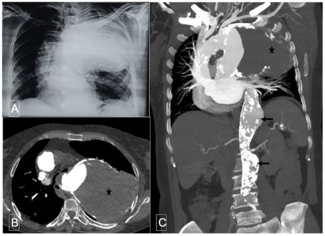

A 61-year-old hypertensive female patient with dyslipidemia presented with hoarseness of voice for the past 2 months. Her physical examination revealed tracheal shift to the right and dullness and decreased breath sounds in the left...